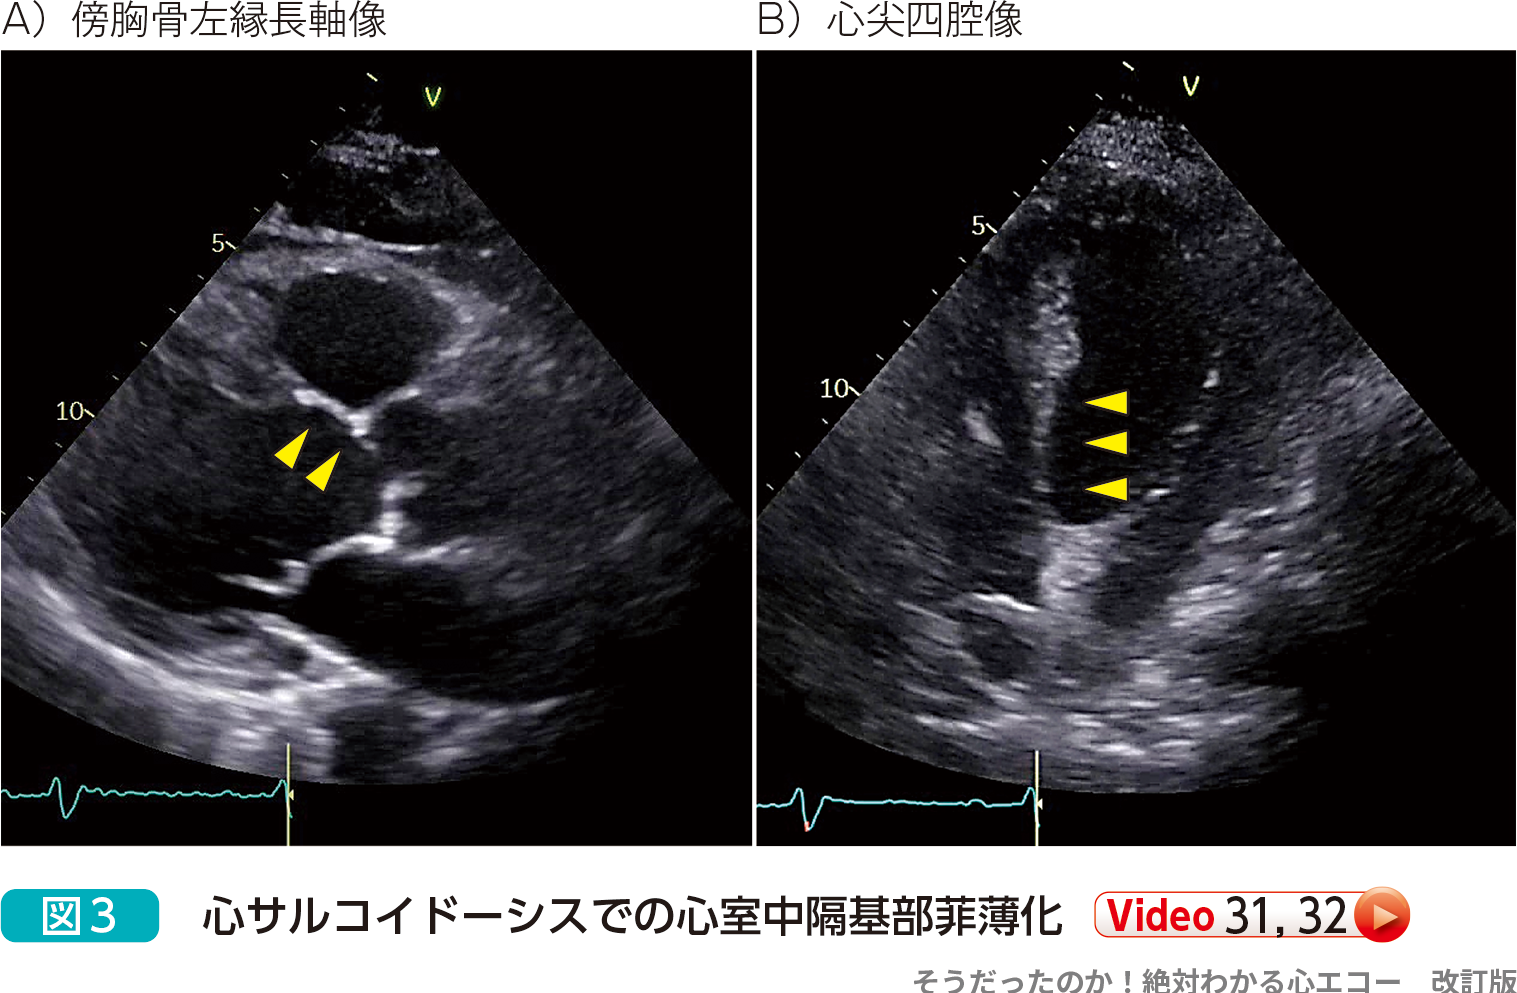

- 傍胸骨左縁長軸像や心尖四腔像で,心室中隔基部の局所的な菲薄化を認めることがあります(図3).特徴的な所見で心サルコイドーシスの可能性が高いですが,このような所見を示さない症例も多くみられます.

- 心室中隔基部の菲薄化による心サルコイドーシスの診断は感度は40%と低いが特異度はほぼ100%と報告2)されており,心室中隔基部の菲薄化があれば心サルコイドーシスの可能性は高いのですが,菲薄化がなくとも心サルコイドーシスは否定できません.